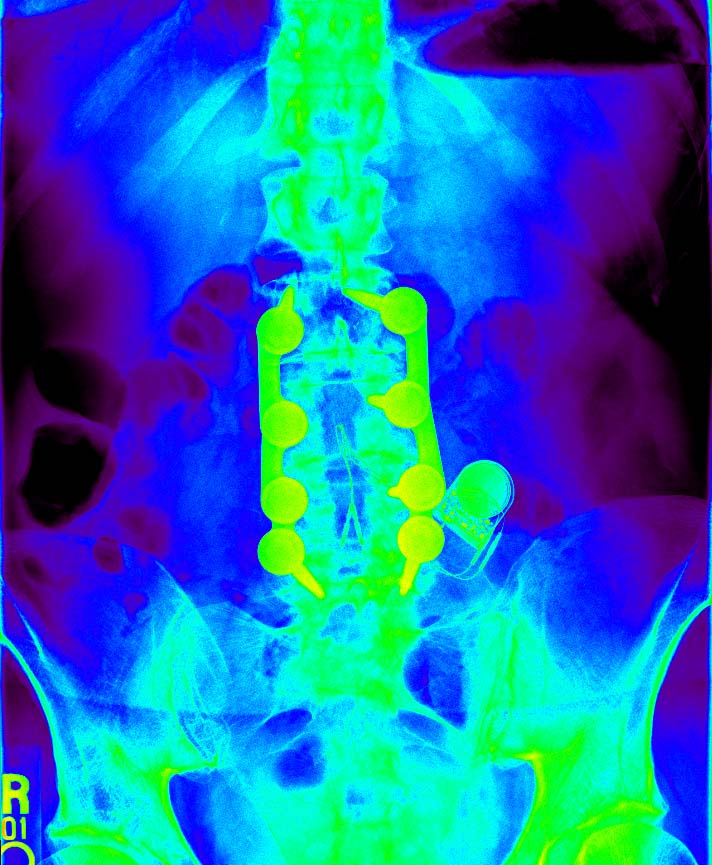

The Wonders of Modern Medicine and Computer Graphics

check out the battery...it's no longer doing anything, but my ashes will be toxic waste.